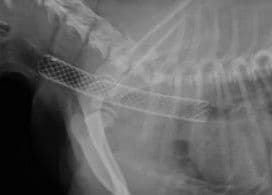

Tracheal Stenting

기관 협착(기관 허탈)으로 인한 호흡 곤란 시 형상기억합금 스텐트를 삽입하여 좁아진 기도를 확장합니다.